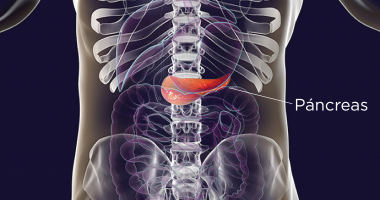

La insulina es secretada a su sangre por su páncreas, que es una glándula localizada detrás del estómago. Si sus células no responden debidamente a la insulina, esto puede provocar que la glucosa se acumule en su sangre. Esto se denomina resistencia a la insulina. Si esto sucede, su páncreas necesita producir más y más insulina para superar la resistencia y controlar los niveles de glucosa en la sangre.